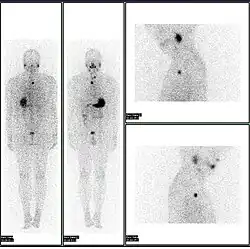

Iodine-123 whole body scan for thyroid cancer evaluation. The study above was performed after the total thyroidectomy and TSH stimulation with thyroid hormone medication withdrawal. The study shows a small residual thyroid tissue in the neck and a mediastinum lesion, consistent with the thyroid cancer metastatic disease. The observable uptakes in the stomach and bladder are normal physiologic findings.